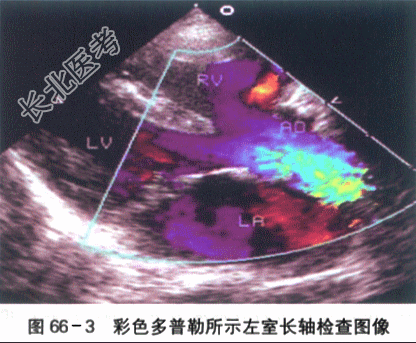

- [材料题] 患儿,男,2岁3个月,因"哭吵后口唇发绀伴气促1h"就诊。患儿入院前1h剧烈哭吵后出现口唇发绀、呼吸急促、家属安抚后无明显改善,送入急诊。出生6月龄前患儿无特殊病史,6月龄后患儿偶有哭吵后口唇青紫,增有剧烈哭吵后呼吸快,口唇发紫加重,安抚后好转;在当地住院发现有心脏杂音,做了一些检查后诊断心脏病(具体不详)。平素活动量少,喜静不喜动,喜抱,偶尔有走路时反复下蹲。目前饭虽少,身高、体重均不及同龄儿。大小便正常。患儿为G₁P₁,孕39周自然分娩。BW3200g。否认孕期感染或服药史,否认围产期窒息缺氧病史。否认家族心脏病或其他遗传病史。体格检查:T37℃,P148次/min,R52次/min,BP78mnlHg/40mmHg,Wt10.1kg,Ht78cm,SaO₂68%。烦躁,全身大汗,口唇发绀,可见杵状指,四肢脉搏稍弱,对称。肺部检查两肺呼吸音粗稍粗,未及明显啰音。心前区饱满,心尖搏动位于第4肋间左乳线上,范围约2cm;HR118次/min,规则,2~3LSB SMⅠ~Ⅱ级,粗糙,P2略增强,无分裂。腹部平软,肝脏肋下2.5cm,质地软。脾未触及。双下肢无水肿。实验室检查(1)心电图检查:窦性节律,右房、右室增大。电轴右偏,Ⅱ导联P波高尖,呈双峰,时限=0.12s。V₁导联QRS波群呈R形,V₅导联QRS波群呈RS形;ST段压低,V₃~V₅导联T波倒置。如图66-1所示。(2)X线胸片检查:右房、右室大。心胸比例0.65,心影呈"靴型"心,心尖圆钝、上翘;肺动脉端内凹,肺血少。如图66-2所示。(3)超声心动图检查:心脏位置及连接正常。右房、右室增大,右室壁肥厚,左室收缩活动正常。主动脉增宽,骑跨于室间隔上50%。左右冠状动脉开口可见,肺动脉瓣及瓣下狭窄,瓣环0.67cm,总干内径1.29cm,流速2.3m/s,右室流出道狭窄肌肉肥厚,过此处血流少,流速约2.8m/s。左肺动脉开口0.82cm,内径0.97cm;右肺动脉开口10.78cm,内径0.85cm。房室瓣开放活动可。房间隔完整。室间隔缺损,对位不良型,双向分流。左位主动脉弓。如图66-3所示。